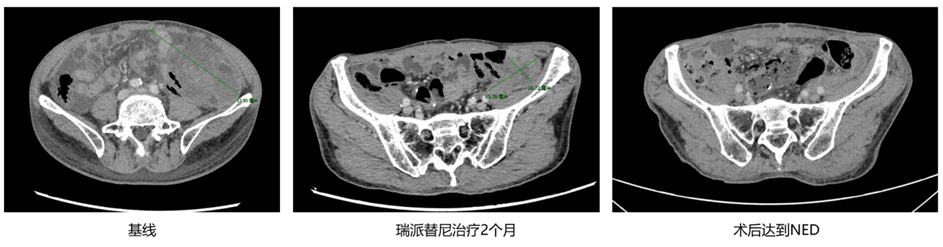

病例二

基本情况

患者,69岁,男,2018年诊断为小肠GIST。

既往手术及一线治疗

◈ 2018年,行小肠GIST手术,术后服用伊马替尼。

◈ 2020年,术后2年停药后复发,而后继续行伊马替尼治疗。

◈ 2023年6月,行“开腹探査术+腹腔粘连松解术+腹腔病损切除术(腹腔肿瘤切除活检)”,术后继续服用伊马替尼治疗,定期复查。

◈ 2025年2月20日,复查CT示左下腹腔团状混杂密度影,范围约147mm×82mm,强化不均匀,提示肿瘤进展。

二线治疗

◈ 2025年2月25日,开始服用瑞派替尼150 mg qd。

◈ 2025年4月22日,首次复查CT示左下腹腔团状混杂密度影,范围约94mm×42mm,肿瘤评效达部分缓解(PR),综合评估后患者已达到手术切除的标准。

◈ 2025年4月27日行腹腔肿瘤切除术+肠粘连松解术。术后达NED状态,继续服用瑞派替尼150 mg qd,期间规律复查,状态良好。